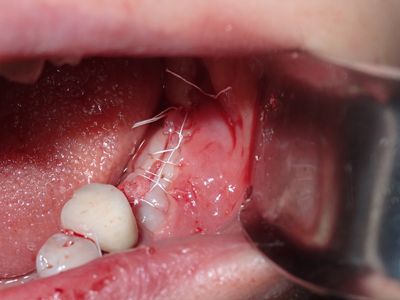

TZeng - vertical bone graft

large crestal defect from previous perio infection, site prepared with small little osteotomies and grafted with sticky bone from allograft/20% xeno, collagen membrane soaked in prf fluid tacked with three membrane tacks, additional fibrin membrane placed.